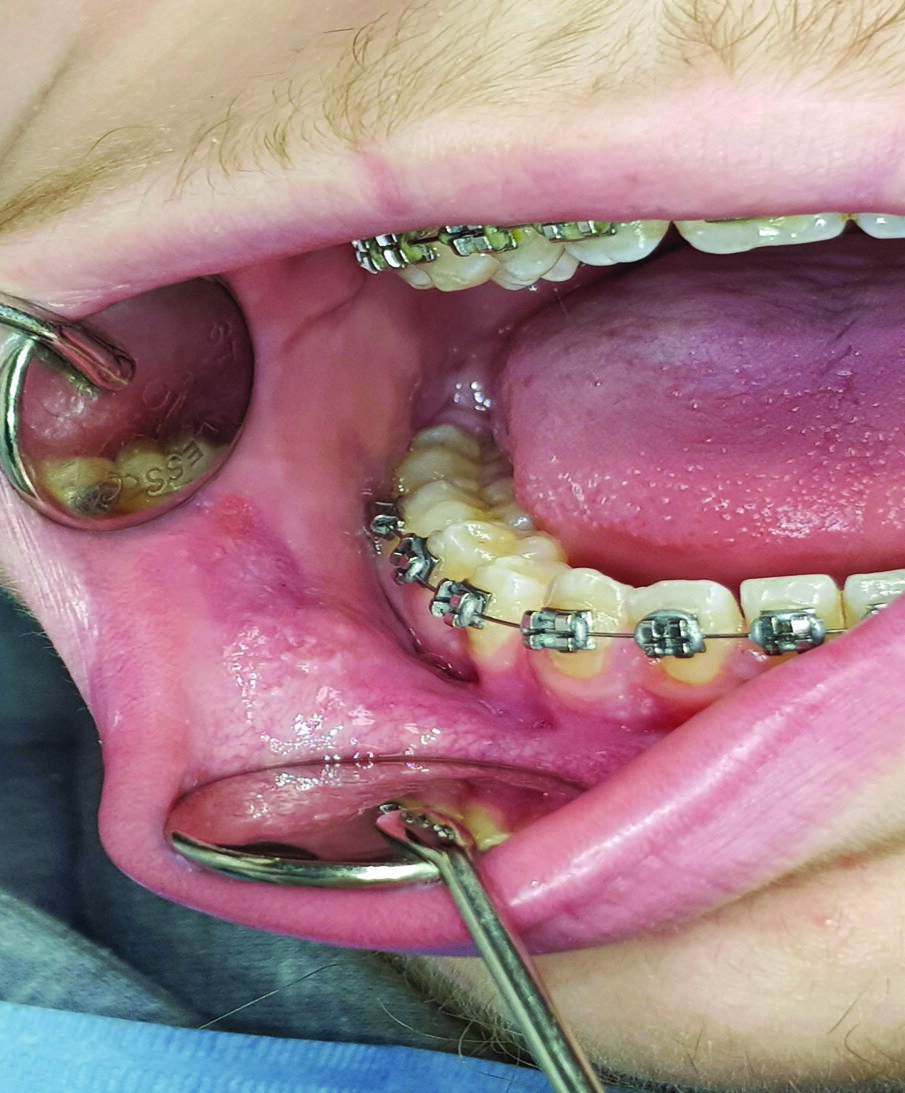

Un paziente maschio di 17 anni, in perfetto stato di salute generale, durante un controllo ortodontico presenta una lesione ulcerativa provocata dallo strofinamento della mucosa buccale con i bracket in corrispondenza del dente n 43-44-45 . Anche in questo caso si prescrive lo stesso collutorio puro per 1 minuto ogni 8 ore per 7 giorni e lo stesso gel orale, descritto precedentemente ogni 8 ore per 7 giorni. Dopo 5 giorni la lesione ulcerativa da strofinamento della mucosa buccale è completamente regredita (Figg. 3, 4).

Fig. 3 - Lesioni ulcerative provocate dallo strofinamento della mucosa buccale con i bracket in corrispondenza dei denti 43-44-45.